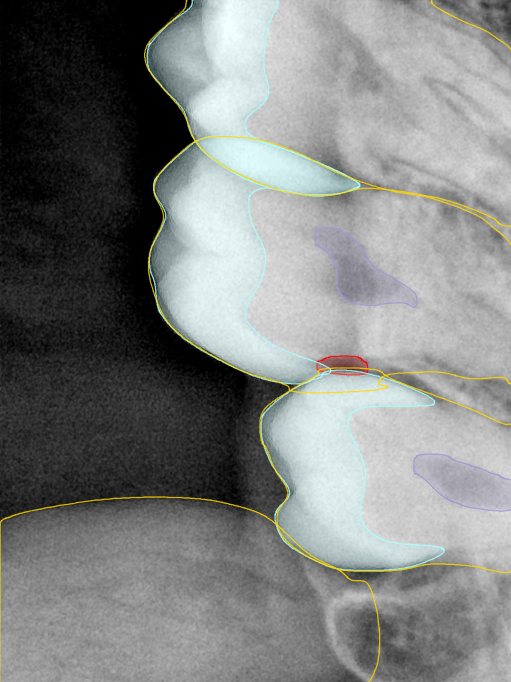

CR/DR 牙齿分割阶段记录

当前进展

- 完成了 CR/DR 牙齿相关分割训练

- 当前结果已经达到阶段预期,但仍有细节问题需要继续处理

相关测试

遇到的问题

- 训练过程中出现过 mask 下移问题

- 部分结果会出现 box 填充异常

- mask 边缘仍然有比较明显的锯齿感

参考